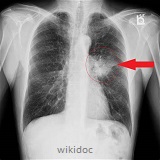

- Link causes and consequences of lung cancer.& emphysema to structure of lungs.

Lung cancer is the commonest form of cancer in developed countries.

The commonest cancer in males (and rapidly increasing in females) is cancer of the and the causes are generally exposure to:

Unregulated mitosis and subsequent cell growth creates tumours.